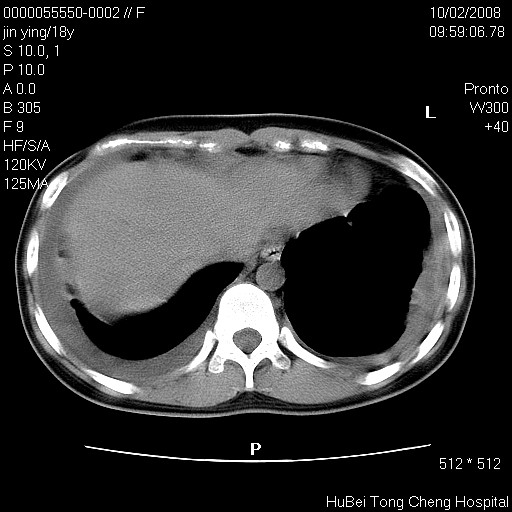

患者 女,18y。发热十余天,伴咳嗽。pe:t39⒈℃,bp 110/80mmhg,p 86次/min。神清,精神欠佳。双肺可闻及少许湿罗音。既往史不详。

临床诊断:肺部感染?

胸部ct轴位平扫(层厚10mm,螺距1.5,重建间隔10mm),图像如下: